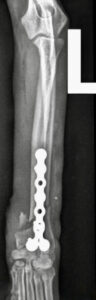

Der Unfall war typisch für Zwerghunde. Aufgeregt war Hugo (Name geändert) so lange zwischen den Beinen seines Halters herumgewuselt, bis dieser ihm aus Versehen aufs Beinchen trat. Die Folge: Der gerade mal 2,3 Kilo schwere Prager Rattler landete mit einem offenen Unterarmbruch auf dem OP-Tisch von Dr. Klaus Zahn. Mit einer feinen, dem zarten Körperbau angemessenen Platte versorgte dieser die Fraktur, und Hugo wurde nach Hause entlassen.

Doch drei Wochen später wurde der kleine Hund erneut im Notdienst vorgestellt: Beim Gassigehen hatte er auf einmal gelahmt. Die Ursache: ein Ermüdungsbruch der Metallplatte. „An Hugo sieht man, was passiert, wenn der tierärztliche Rat zur Ruhigstellung nicht befolgt wird“, sagt Dr. Klaus Zahn. „Übermäßige Aktivität hatte die Platte überlastet.“ Denn der Prager Rattler durfte viel zu früh wieder frei im Zimmer herumlaufen und sogar vom Sofa springen. „So kleine Hunde gehören für vier bis sechs Wochen in einen Laufstall, damit die Knochen stabil heilen können“, erklärt der Orthopäde.